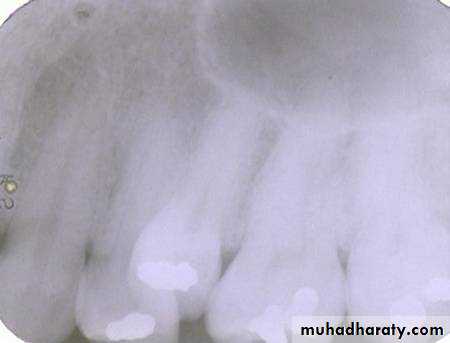

Maxillary PA

BWMandibular PA

Vertical movement of the tube head and x-ray beam

In moving from the maxillary periapical to the bitewing and from the bitewing to the mandibular periapical, the tube head moves down and the beam is redirected upward (opposite direction; decreased vertical angulation).